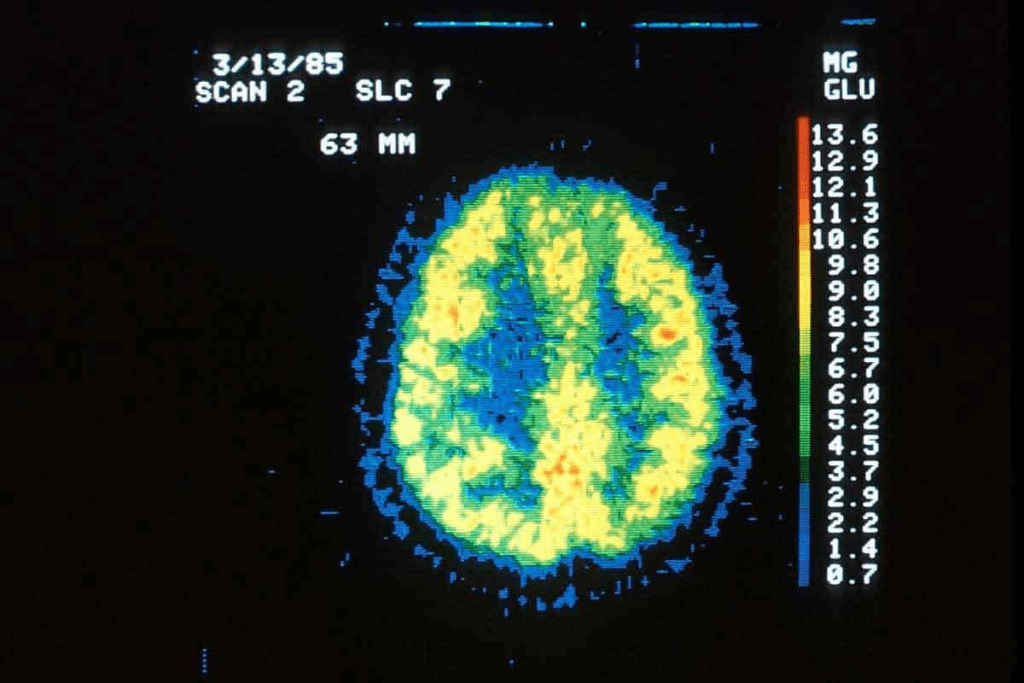

PET scans help us see how different parts of the brain work. They show changes in blood flow and sugar use. This helps us tell apart a depressed brain from a healthy one.

PET scan tech uses a radioactive drug, called a tracer, injected into a vein. This tracer builds up in active areas of the body. In brain scans, it’s often linked to glucose, as the brain uses a lot of it.

By tracking the tracer, the PET scan spots brain activity hotspots. This is key to seeing how the brain works in both healthy people and those with depression.

The type of tracer used in PET scans matters a lot. Different tracers show different brain functions, like glucose use or neurotransmitter activity. For example, Fluorodeoxyglucose (FDG) shows glucose metabolism, helping us understand brain energy use.

By studying PET scan data, experts can find brain activity patterns linked to depression. These include changes in blood flow and brain region activity. Knowing these patterns helps in creating better treatments and tests.